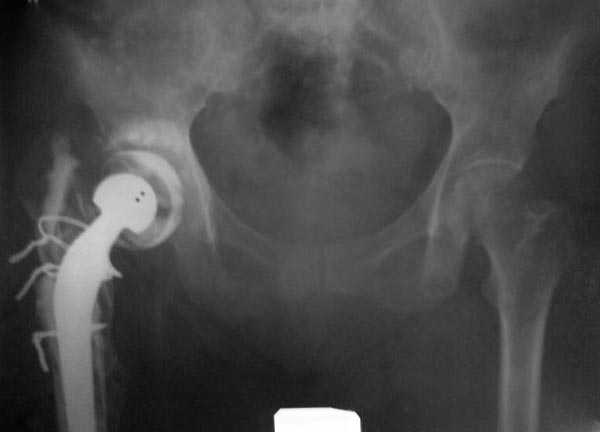

В дальнейшем заменил бы наружный фиксатор из частей аппарата Илизарова на более стабильный - стержневой фиксатор таз-бедро. В тазу можно применить полукольцо стержнями за крыло таза и дистально 2-3 стержня между передней и боковыми головками четерехглавой мышцы. Дельтовидная рама сверху вниз усилит конструкцию.

Можно на аппарате или на вытяжении немного дотянуть для создания запаса длины.